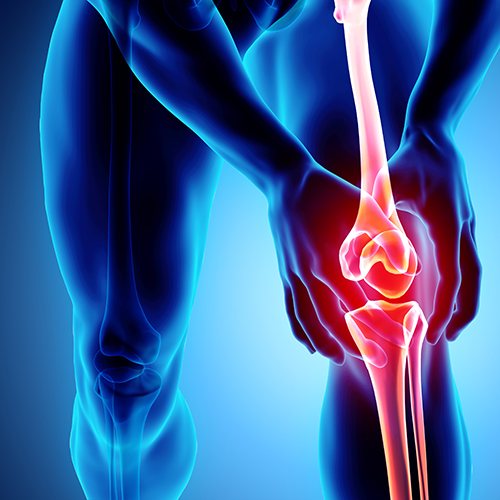

University of South Australia researchers are a step closer to finding a new biomarker for osteoarthritis, a painful condition which affects more than two million Australians and costs the country an estimated $23 billion a year.

University of South Australia researchers are a step closer to finding a new biomarker for osteoarthritis, a painful condition which affects more than two million Australians and costs the country an estimated $23 billion a year.

Using new state-of-the-art imaging techniques to identify signs of osteoarthritis (OA), UniSA scientists are learning more about changes at the molecular level which indicate the severity of cartilage damage.

“It is one of the most common degenerative joint diseases, yet there are limited diagnostic tools, few treatment options and no cure.”

Osteoarthritis affects an estimated 2.2 million Australians and more than 300 million people worldwide, with those aged over 45 most at risk. Being female, overweight, and having existing joint injuries increases the risk of getting OA.